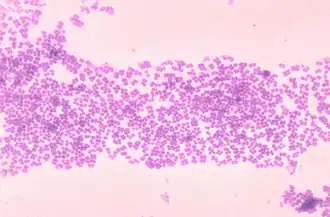

Micrococcus é um gênero de bactérias do filo Actinobacteria. Normalmente, não são patogênicos, e podem ser essenciais para manter o equilíbrio da flora bacteriana na pele.[1]